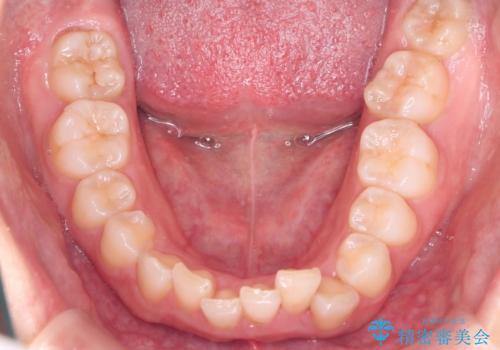

- 上の前歯の出っ歯と前歯の深い咬み合わせを治したいとのことで来院された患者様です。

上顎の歯は後方移動とIPR(歯と歯の間を削る)によって口元が引っ込むように、下顎は歯列全体の拡大とIPRによって上顎とバランスよく咬み合うように設計し、インビザラインにより治療を行うこととしました。

上顎歯列の後方への移動量が多く、右側の奥歯の咬み合わせを改善する必要もあったため、治療には長期間を要しました。